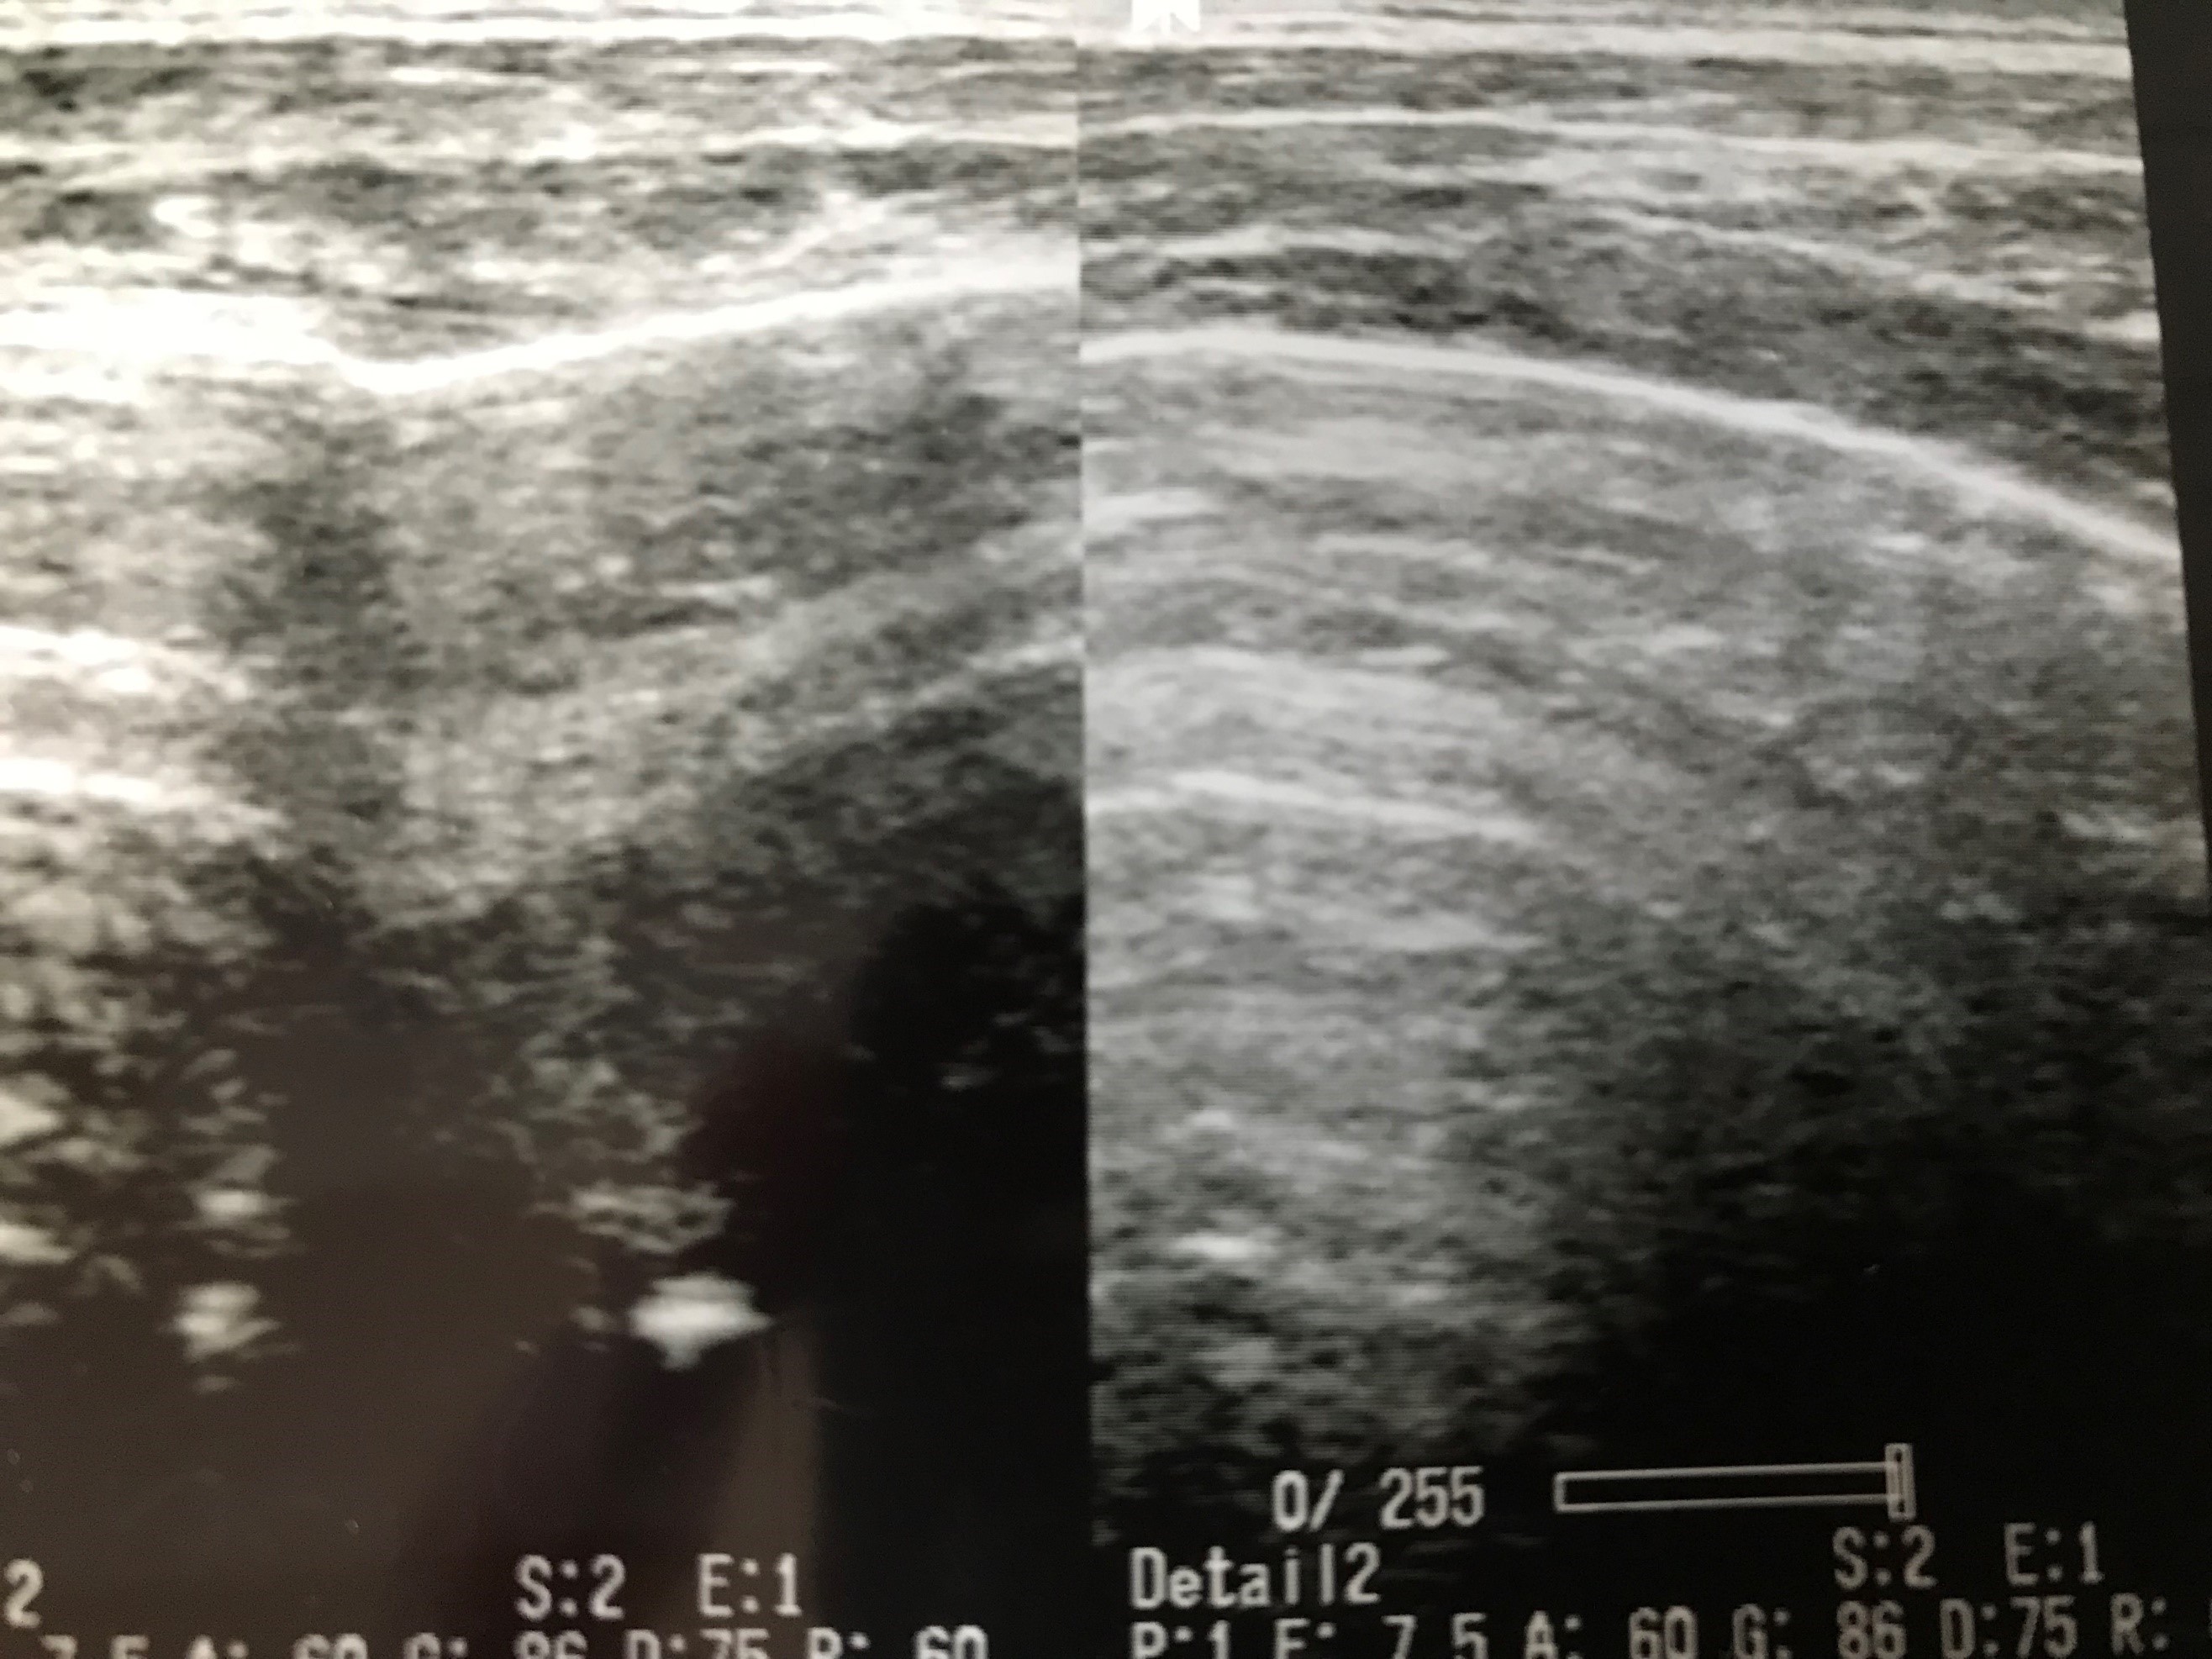

16才 女性 バスケットボールの試合中内反強制され受傷。エコーで骨片様の画像が確認できたため整形外科でレントゲン撮影依頼し、関節鼠を確認。